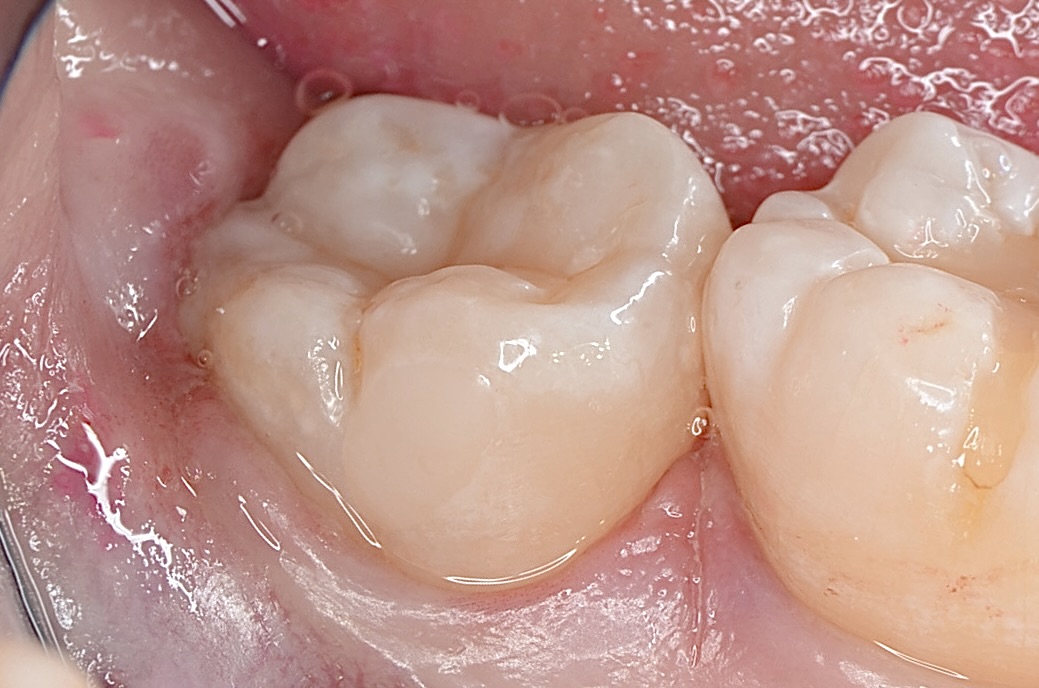

After

ダイレクトボンディング

天然歯の自然な形態を模倣してレジンを充填しました。 -

研磨後

研磨をしっかり丁寧にすることで、レジンと歯質の段差を修正し、虫歯になりにくくします。